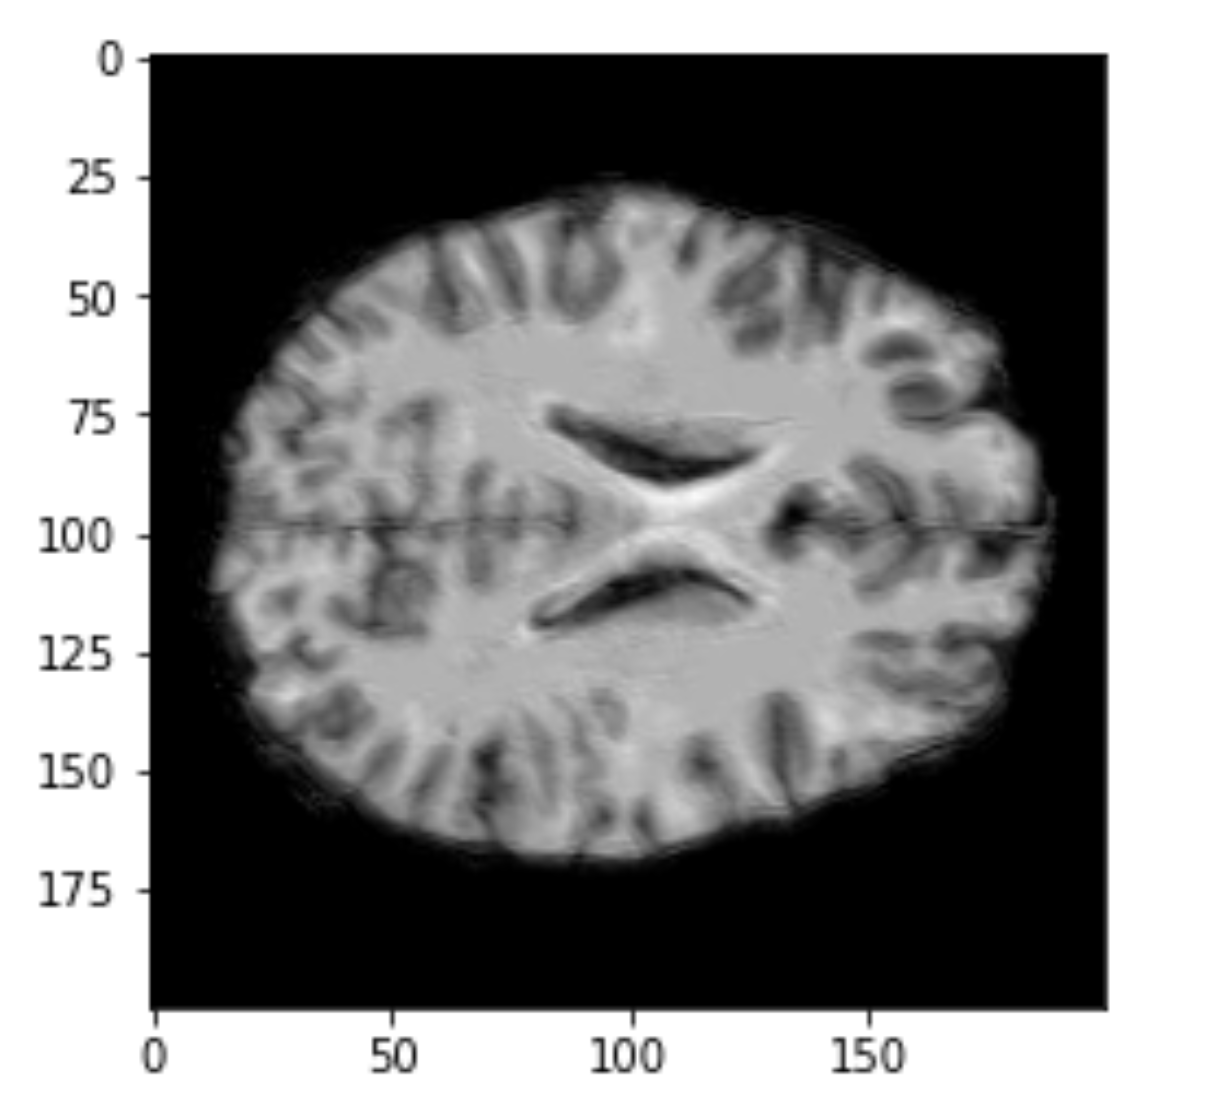

Volumetric representation

Voxelzed object

Brain slices

Data exploration

Cropping

cropped = data[50:205,60:225,30:225] #155x165x195

data = img.get_data() #256x256x256

256x256x256

155x165x195

50x50x50

Original

Cropped

Resized

Input sizes